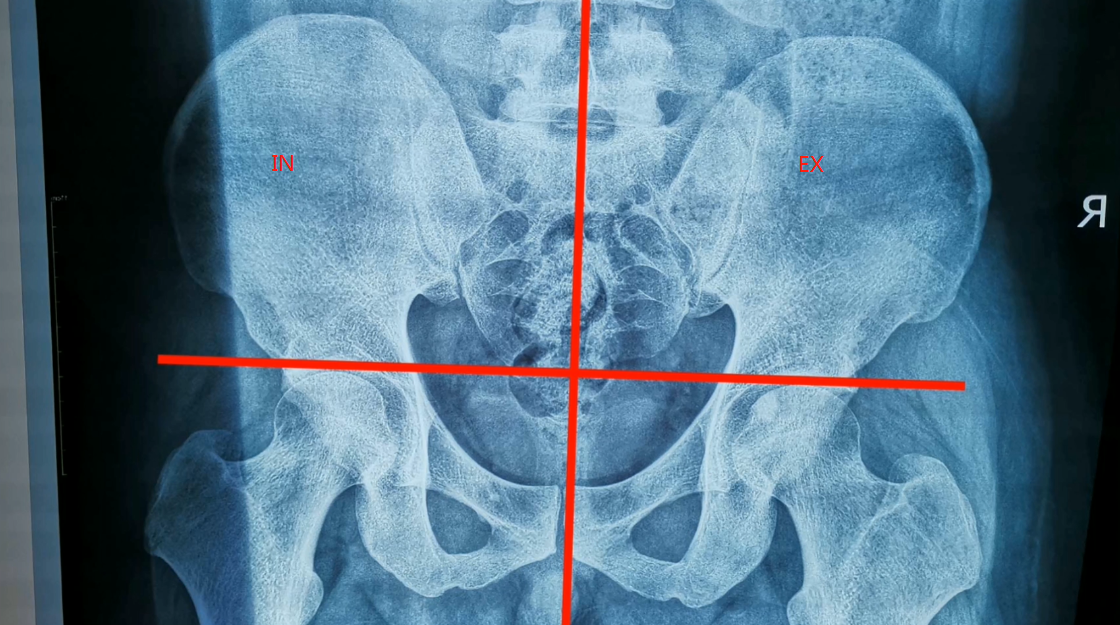

骨盆矫正之如何在x光找到骶骨的错位骶骨错位矫正